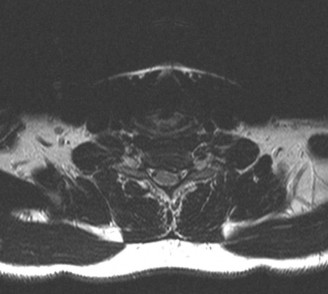

fractures of the anterior or posterior elements. The hallmark feature is a translation deformity that can be noted by misalignment of the vertebral bodies in the coronal and/or sagittal planes. A lumbar spine MRI is obtained, images from which are shown inFigures 1–34 and 1–35. Based on the information presented, the type of neurological injury is best characterized as which of the following? 1. Cauda equina injury

Figure 1–34

Figure 1–35

The correct answer is (A). The MRI demonstrates the L2 fracture with canal compromise. In this patient, the conus medullaris of the spinal cord terminates at the T12–L1 level. The fracture is at the L2 level. Thus, the neurological injury is at the level of the cauda equina, distal to the conus medullaris and spinal cord. The patient’s neurological examination is consistent with this type of injury with the presence of lower extremity weakness, intact rectal tone, and perineal numbness, though this can vary.